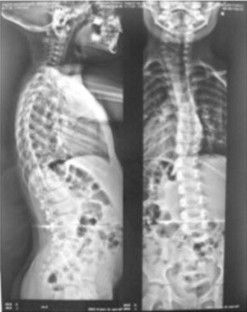

Fig. 3